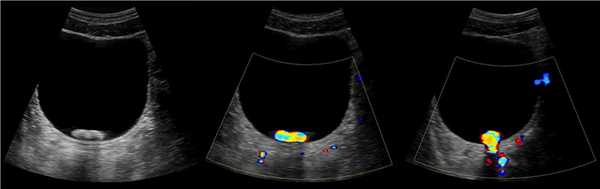

Рисунок. На УЗИ камень в мочевом пузыре — гиперэхогенное включение с акустической тенью, при ЦДК артефакт мерцания. На поперечном срезе в положении лежа на спине (1, 2) возникает сомнение — это два округлых или один вытянутый камень. При повороте на бок (3) определяется единственный округлый конкремент меньшего размера, что было расценено как зеркальный артефакт.

Иногда опухоли мочевого пузыря обнаруживаются при трансректальном ультразвуке, который проводился для оценки простаты. Небольшие опухоли мочевого пузыря в области тригона или шеи особенно хорошо проявляются при трансректальном ультразвуке (рис.5). Цветной допплеровский ультразвук (CDUS) показывает васкуляризацию опухоли и часто показывает линейные сосуды в ножке опухоли. CDUS полезен для дифференциации опухоли из сгустка крови, показывая отсутствие васкуляризации в сгустке. В одном исследовании сосудистая опухоль, наблюдаемая на CDUS, не имела отношения к стадии опухоли или гистопатологическому классу.